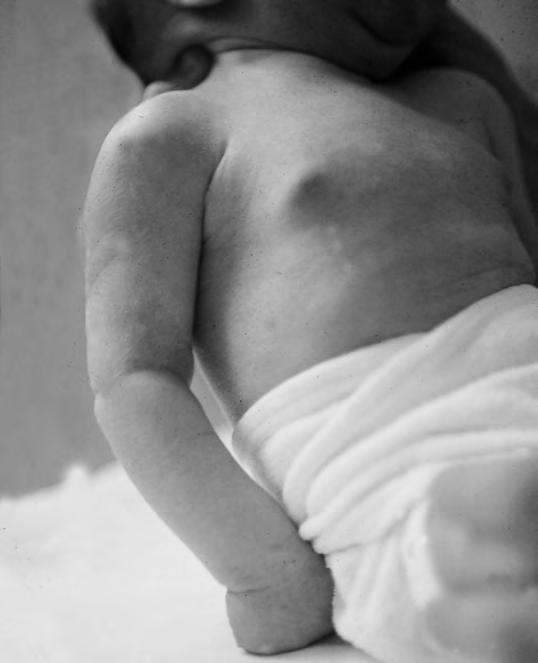

Adiponecrosis subcutánea del recién nacido

Es la necrosis del tejido celular subcutáneo. Se observa a nivel de mejillas (Fig. 2.29.1), nalgas, espalda y, a veces, en muslos. Consiste en placas redondeadas, como monedas grandes, en las cuales se comprueba por palpación una zona dura, infiltrada, recubierta por una piel algo enrojecida y adherida a ellas; en casos más excepcionales pueden ser unas placas de mayor tamaño, que ocupan gran parte de las nalgas o de la espalda. Es debida a la isquemia producida por compresión prolongada del tejido graso con los relieves óseos de la madre, por la acción del fórceps o por la presión de las manos del tocólogo y también por la acción del enfriamiento, como ocurre en algunos lactantes ya mayorcitos que, por la acción del frío, a veces presentan placas de endurecimiento parecidas a las del RN, pero siempre más leves y sin tendencia a la necrosis. En algún caso estas placas se abren al exterior con eliminación de un material semejante a grasa necrosada, aunque su pronóstico es bueno, regresando sin tratamiento específico.

Muy raramente puede observarse la calcificación. Hay que distinguir estas lesiones del escleredema y esclerema, en prematuros, y de las adiponecrosis por inyección medicamentosa (gluconato cálcico, perfusiones hipertónicas).